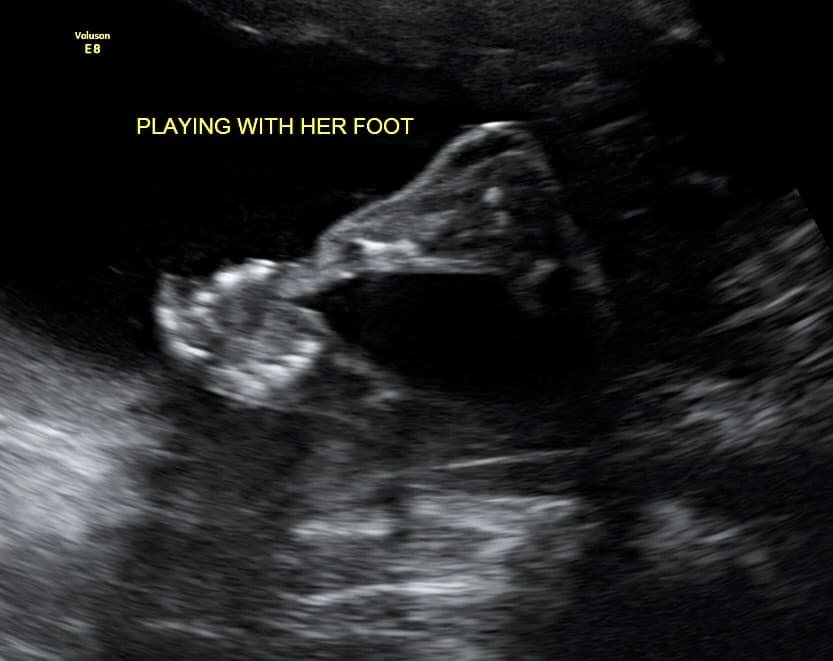

At Magnolia Fetal Imaging, we provide a warm, relaxing environment where you can bond with your baby through advanced 3D/4D & HD ultrasound technology. Our studio focuses on capturing precious keepsake moments for families — gender reveals, early looks, and high‑definition images you will cherish for a lifetime.

All sessions are non‑diagnostic and designed purely for bonding and keepsake entertainment.